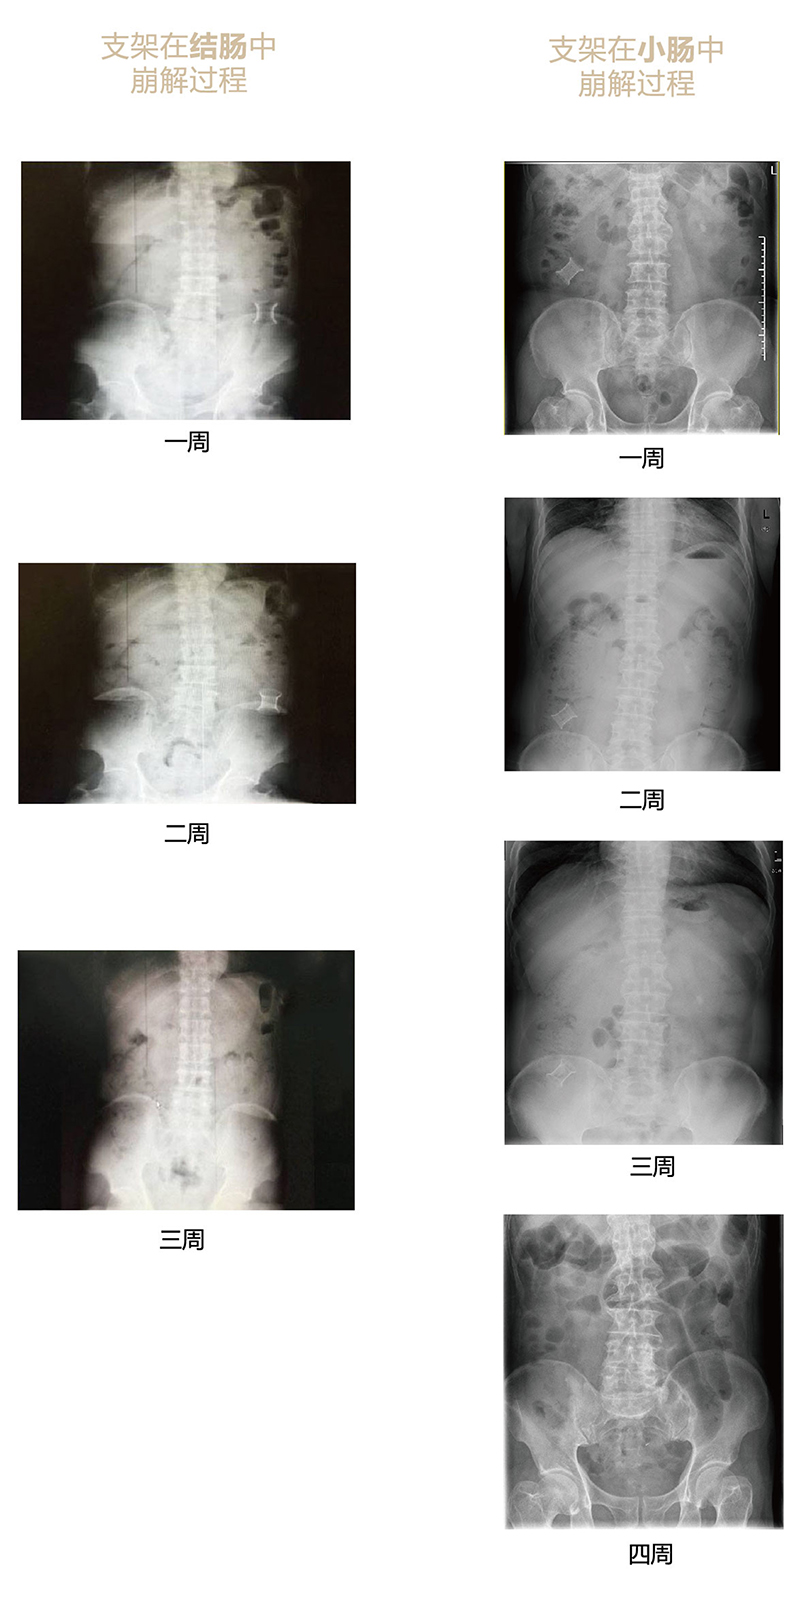

“可崩解腸道吻合器”由聚乙醇酸(PGA)與硫酸鋇按重量比7:1混合注塑制成,在X線下顯影,可動態(tài)追蹤可崩解腸道吻合器(支架)在腸道內(nèi)崩解過程。

為解決該問題,蔡秀軍教授在“支架法空腔臟器吻合技術”的理念基礎上,又發(fā)明了“蔡氏腸轉流術”,這是一種應用“可崩解腸道吻合器HB型(可崩解腸轉流支架)”(發(fā)明專利號:201910794214.3),的支架法腸道轉流術,此創(chuàng)新術式既能保護低位吻合口,更避免了回納術??杀澜饽c轉流支架在直腸癌根治術中植入遠端回腸,可確保完全阻斷腸腔,用腸造瘺管在轉流支架近端行腸造瘺,起到完全轉流的作用。腸轉流支架在二至三周內(nèi)逐漸崩解,并在四周內(nèi)完全排出體外,恢復腸道通暢后拔除造瘺管,避免了傳統(tǒng)造口回納的二次手術。該創(chuàng)新術式具有方法簡單、吻合時間短、人體內(nèi)無異物永久殘留、不破壞吻合口粘膜下血管,并能預防吻合口漏、可避免人工肛門留置及二次手術、治療周期可縮短至二至四周、患者生理心理創(chuàng)傷顯著減少。